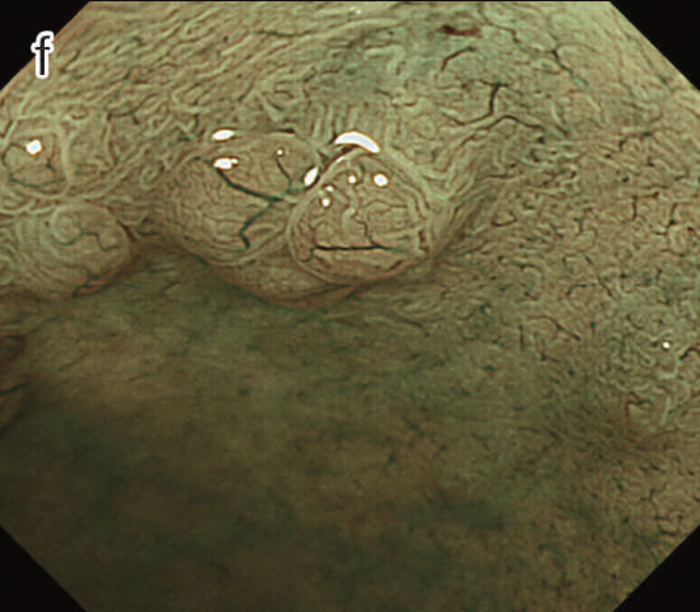

図12 Non-polypoid lesionの内視鏡所見

- 白色光観察

- インジゴカルミン散布像:境界がより明瞭に認識できる。

- 酢酸インジゴカルミン混合液(AIM)散布像:病変全体と周辺粘膜とのコントラストが明瞭となる。

- NBI非拡大観察像:非拡大においても境界の認識は比較的容易となる。

- NIBI拡大観察像:病変中心部では拡張した血管を認める。

- クリスタルバイオレット染色拡大観察像:病変中央では大腸不動の拡張したpitを認める。gの病変辺縁ではpit構造の違いにより周辺粘膜と病変の境界が認識できる。